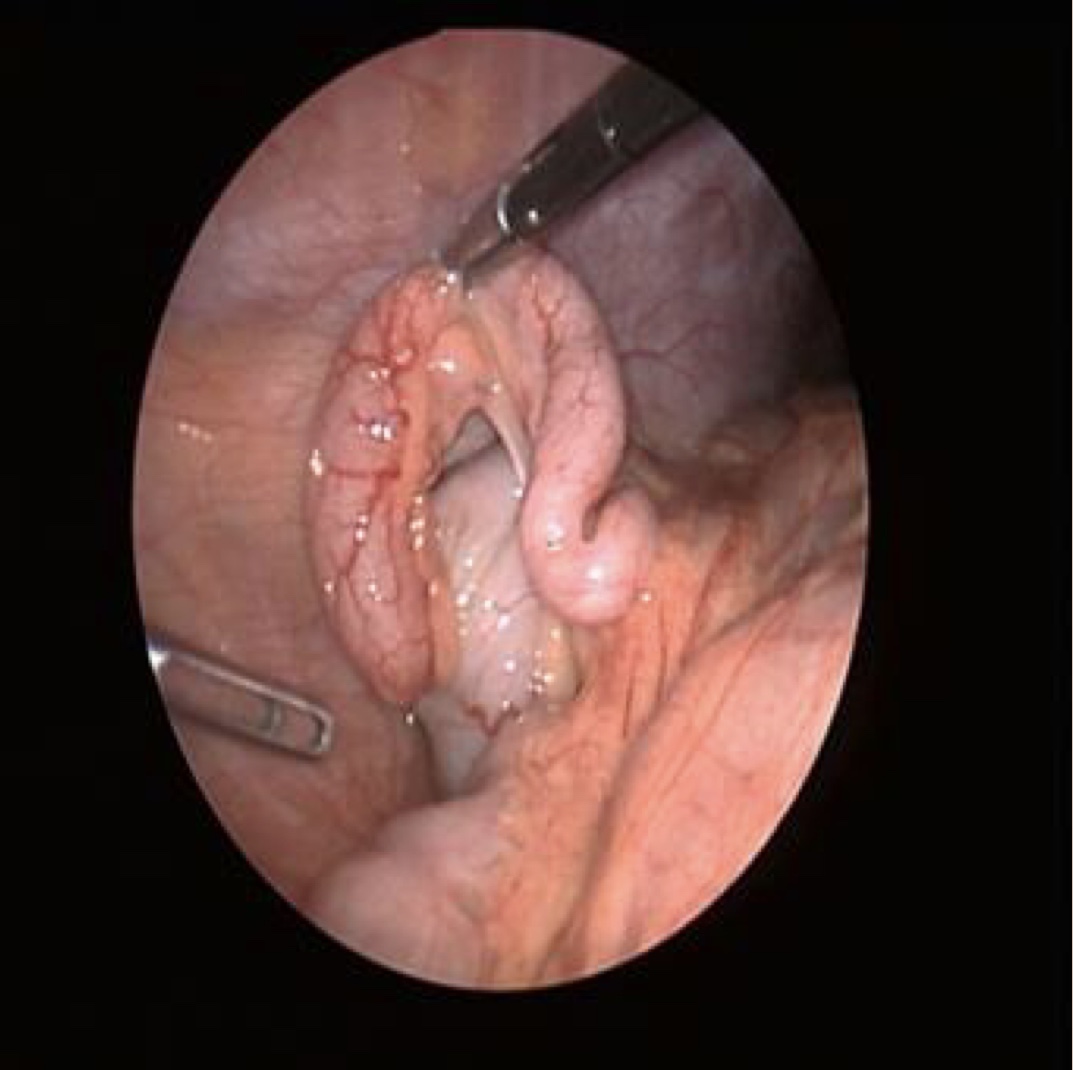

Laparoscopic Appendicectomy

Video for Visual Learners

Audio for Acoustic Learners- Laparoscopic Appendicectomy

AI Curated Slide Deck for Laparoscopic Appendicectomy

AI Collaborative Simulated Case Scenario Discussions on Laparoscopic Appendicectomy

AI Curated Video Summary of Laparoscopic Appendicectomy